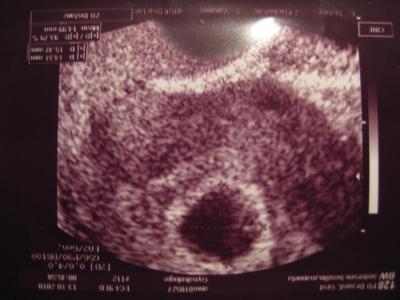

Heute früh war ich wieder zum US (5+5 SSW) und es war eine 5,5 cm große Fruchhöhle mit Dottersack zu sehen. Der Dottersack hockt nur in der Ecke und wollte nicht wirklich mit auf´s Bild. HCG ist auch tüchtig gestiegen und zum Glück ist es nur eins...zwei wären kein Weltuntergang gewesen, aber eins ist mir ehrlich gesagt viel viel lieber. Am 27.10. hab ich dann wieder Ultraschall....ich muss alle 2 Wochen hin, weil ich Risikoschwanger bin und ich enger kontrolliert werden muss. Anbei das Bildchen von Zwergis Fruchthöhle :-)

Bild zu Bericht vom heutigen US mit ersten Bildchen - Kinderwunschbehandlung